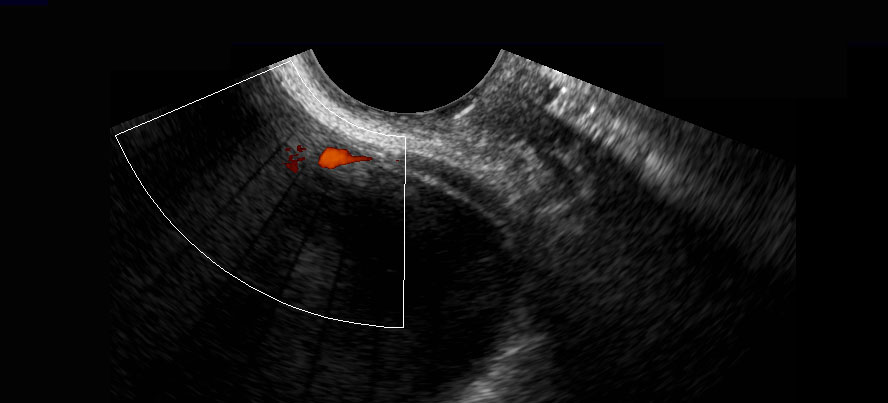

Ở người phụ nữ này, đoạn niệu quản xa bình thường (đầu mũi tên) đã được hiển thị, bao gồm cả “hiện tượng tia phụt” của niệu quản khi sử dụng Doppler. Lưu ý khoảng cách nhỏ giữa đầu dò âm đạo và niệu quản đoạn xa.